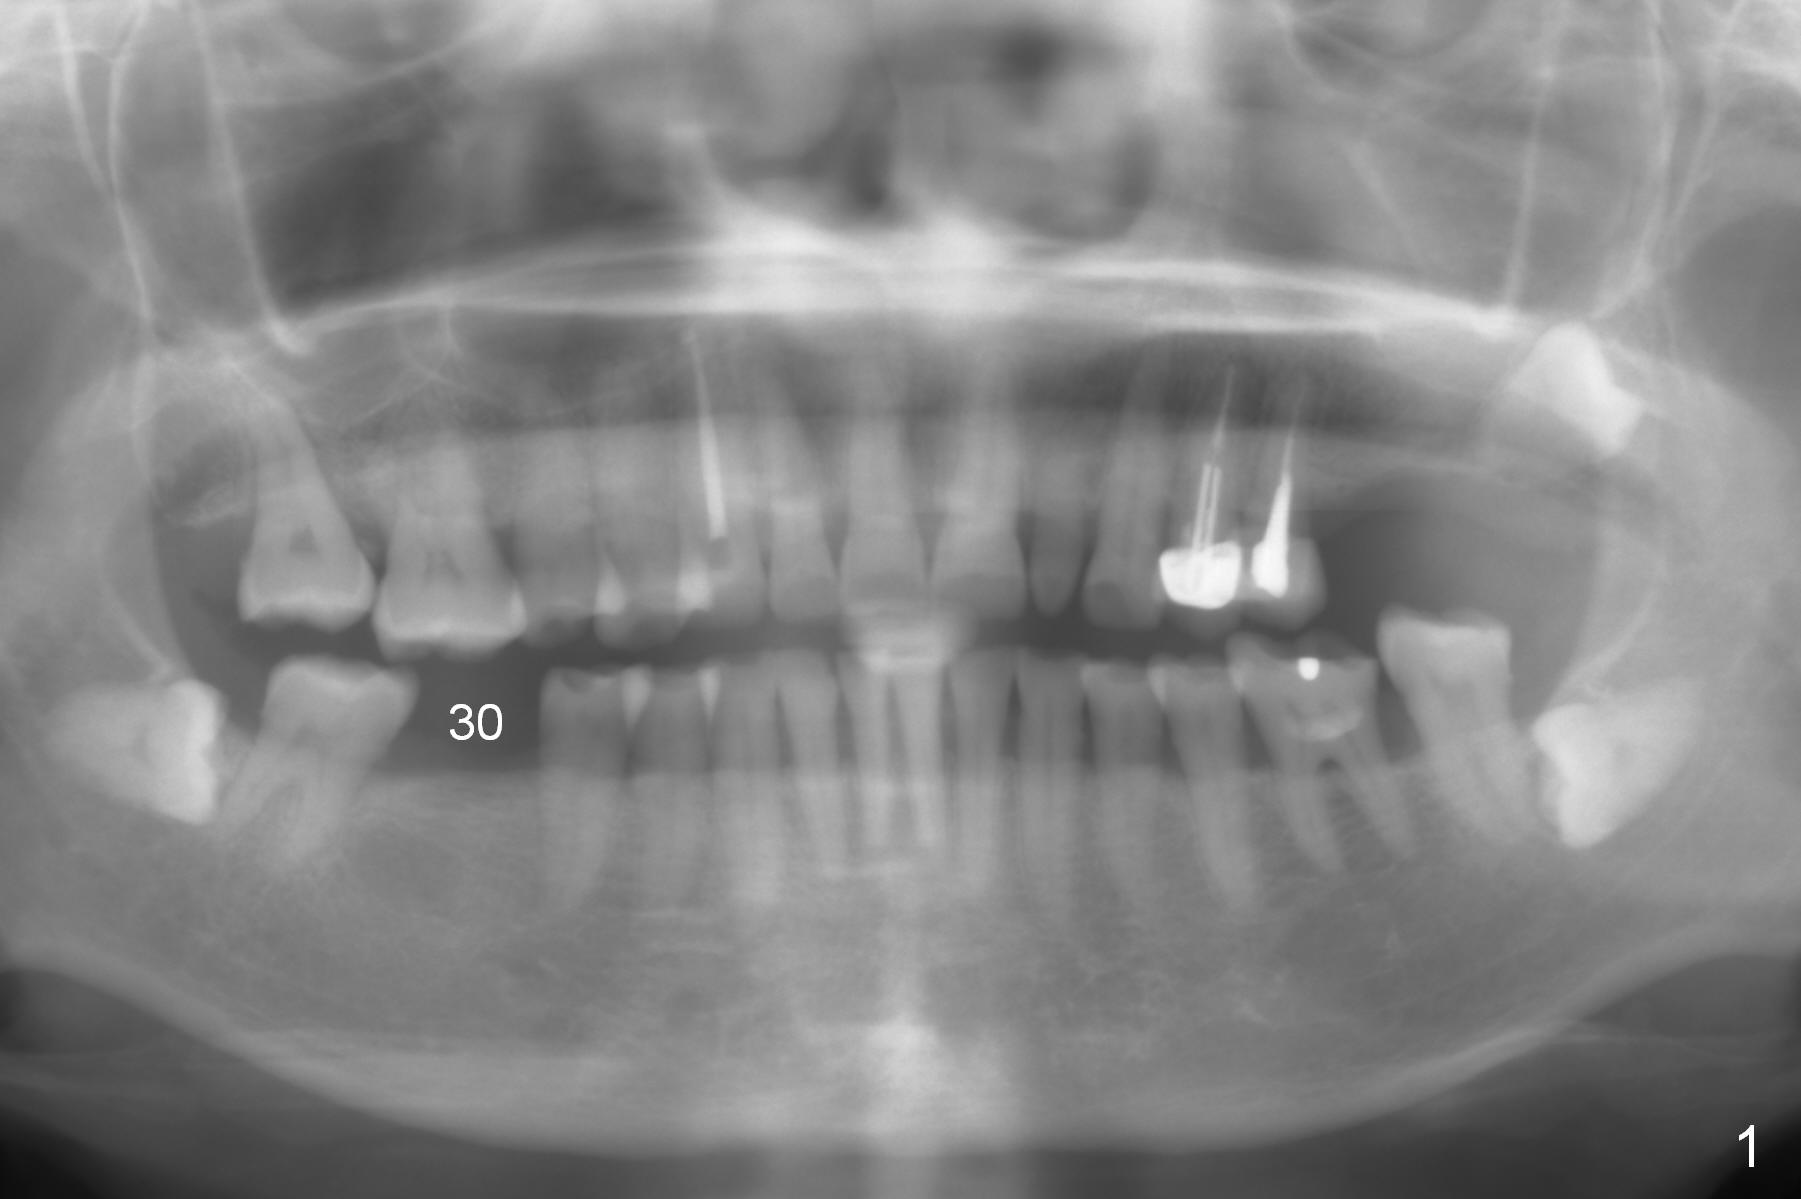

Flapless for Moderate Ridge

A 57-year-old woman has 3 missing molars, including #30 (Fig.1). Although she looks skinny, clinically the ridge is moderately wide. Magic Split will be used for access (flapless) and bone density testing. From PA, the bone density does not seem to be low (Fig.2). Use the 1.6 mm drill without stopper for further bone density testing. The initial depth will be 15 mm (gingival level, Fig.3). After PA confirmation of the trajectory, use 3.8 mm Magic Drill for 15 mm. Try 4.5x11 mm dummy implant, followed by PA. When an abutment is placed, trim the opposing surpraerupted tooth if necessary (Fig.3 arrow).